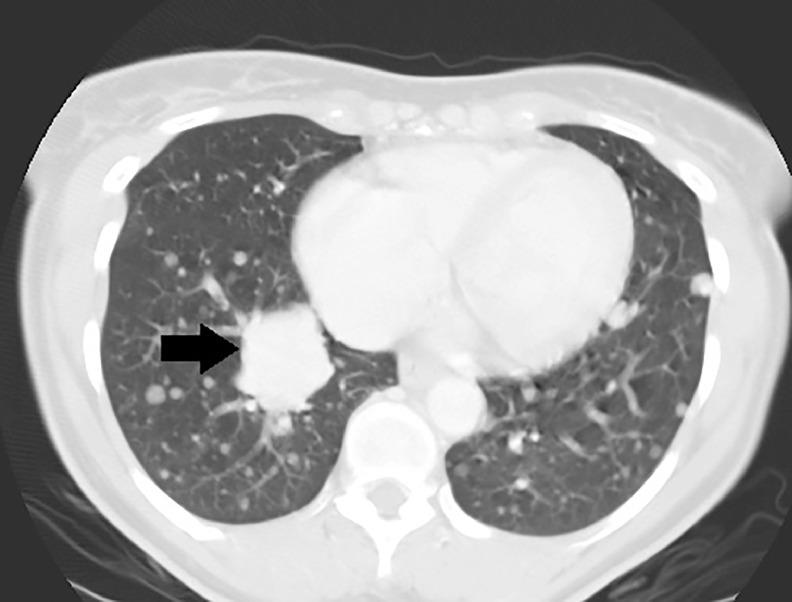

CT findings of pathology proven benign metastasizing leiomyoma.

Benign metastasizing leiomyoma, originally reported in 1934 by Paul Steiner is a rare entity with less than 150 documented cases. While this entity has a favorable prognosis, without proper recognition it could be misdiagnosed as advanced stage metastasis. This case report discusses the relevant imaging findings of a case of benign metastasizing leiomyoma involving a 46-year-old woman which was detected in a preoperative work-up for hysterectomy. The patient presented with chronic cough for 2 years and a history of uterine fibroids. Because benign metastasizing leiomyoma was considered in this patient who presented with lung nodules and pelvic masses, a biopsy of the salient lesions was rapidly performed and enabled pathology to confirm a diagnosis of this entity. This case examines the differential diagnoses associated with multiple pulmonary nodules and provides an example of why the radiologist should consider benign metastasizing leiomyoma in that differential when these findings are identified in perimenopausal women.